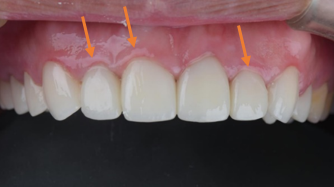

治療後 :牙冠增長術修整牙齦+貼片覆蓋,修飾牙齒形狀及顏色,

- 臨時假牙更換為固定的全瓷冠

- 前牙顏色不均+長時間錯咬導致門牙切端形狀不一。 做前牙貼片覆蓋,一口乾淨帥氣的白牙就出現啦!!!

- 前牙原錯咬,上排牙齦高低不一,做〖 牙冠增長術 〗 修飾牙齒形狀。

笑齦改善,閃亮亮的白牙出現啦。